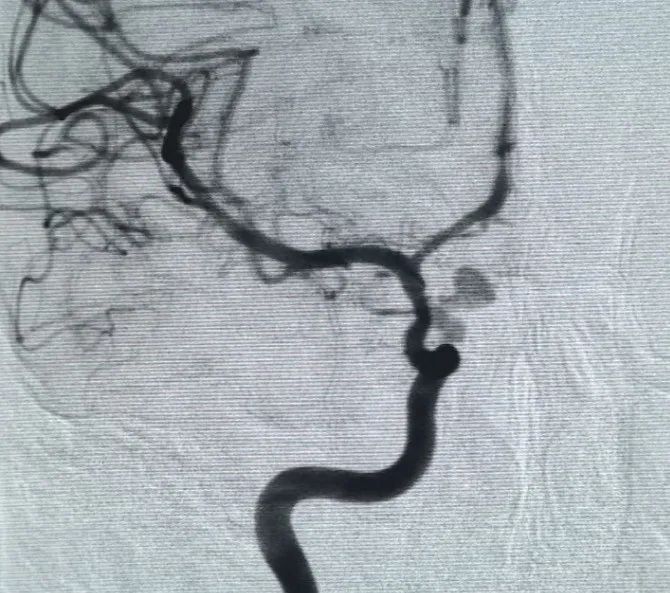

パーフィラー®3mm × 6 cmの拡大可能なコイルおよびパーフィラー®次いで、3mm × 2 cmの拡張可能なコイルを配置して、首の咬合を完了させた。 その後、ヌバ®フローダイバーター (TJED-D-5.0-16) を投与し、動脈瘤の首全体に展開しました。 前後および横方向の両方のビューでの追跡血管造影により、優れたカバレッジ、良好な壁の配置、および明確な放射線不透明度が確認され、顕著なコントラストの停滞が確認されました。

手順は合併症なしでスムーズに完了し、患者は神経学的欠損なしで回復しました。